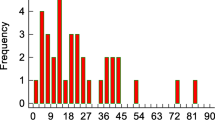

Residual GM volume differences in the posterior cerebellum at 3 months post-SAH are related to patients with cognitive impairment. (A) GM volume values in the significant cerebellum residual abnormalities. While the values are on average similar between those patients without cognitive impairment and the healthy controls, they are clearly higher in those with cognitive impairment (calculations done using the weighted average in the supra-threshold cluster shown in B). For visualization only, we also present those same values for the first two timepoints (< 72 h post-SAH and 5–10 days post-SAH; in greyed areas). (B) Results from the regional GM analysis (VBM) at 3 months post-SAH. Patients have higher GM volumes in the posterior, cognitive cerebellum (red-yellow, p < 0.016 TFCE-corrected) encompassing regions of crus I, crus II and VIIb bilaterally (as shown in C, in yellow, green and pink, respectively from a probabilistic atlas). L is R.

In the cerebellar region of interest (ROI) defined by this significant, apparent increase in GM volume in the entire patient group compared with the healthy controls (“scan3-ROI”), those patients with cognitive impairment had higher GM volumes indeed compared to those without, who seemed to have GM volumes similar to those of healthy controls (Fig. 3A). Cohen’s d calculated between patients with and without impairment for the GM volume of the cerebellum scan 3-ROI was 0.72—suggesting a medium to large effect size difference between the two groups17.